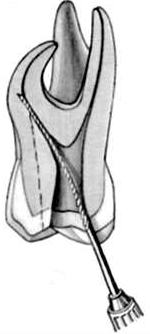

El ensanchador Gates Glidden tiene un extremo cortante corto, en forma de llama, con hojas cortantes laterales levemente espiraladas con ángulo muy inclinado respecto de la vertical. Generalmente tiene una pequeña guía no cortante en su extremo para minimizar su potencial de perforación de la superficie radicular.  Ver imagen izquierda

La cabeza cortante está conectada al vástago por un fino y largo cuello. Está numerado del 1 al 6 mediante marcas en el tallo del instrumento. Se utilizan para la ampliación y conformación de los conductos después del limado seriado y ensanchamiento con limas, en sus tercios cervical y a veces hasta el tercio medio. Ver imagen derecha

Los taladros Gates Glidden están diseñados con un punto débil en la parte del eje más cercana a la pieza de mano, de forma tal que el instrumento fracturado pueda ser retirado fácilmente del conducto.

Se fabrican de acero inoxidable y con un largo desde la punta hasta el contrángulo de 18 mm.